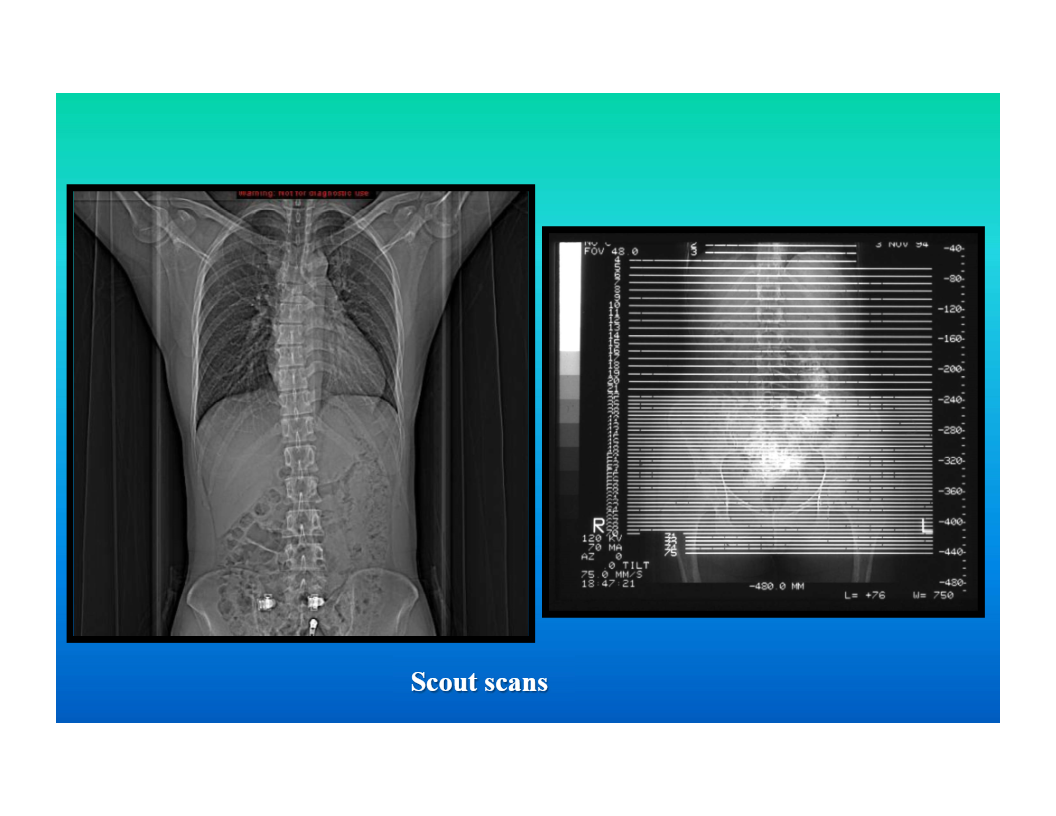

computer tomography

computer algorithm generates cross sectional images based on x-ray beam array passed through the body

all body parts can be imaged

image descriptor is density

intravenous (iodine based) and oral (barium or iodine based) contrast may be used to enhance anatomic and tissue differentiation